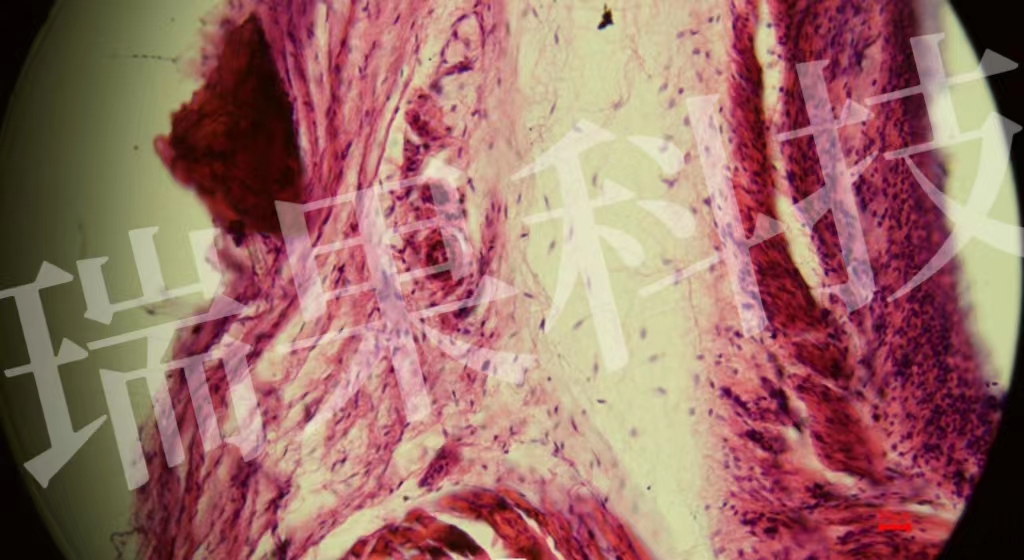

HE染色:苏木精 - 伊红染色法 ( hematoxylin-eosin staining ) ,简称HE染色法 ,石蜡切片技术里常用的染色法之一 。苏木精染液为碱性 ,主要使细胞核内的染色质与胞质内的核酸着紫蓝色 ;伊红为酸性染料 ,主要使细

HE染色:苏木精 - 伊红染色法 ( hematoxylin-eosin staining ) ,简称HE染色法 ,石蜡切片技术里常用的染色法之一 。苏木精染液为碱性 ,主要使细胞核内的染色质与胞质内的核酸着紫蓝色 ;伊红为酸性染料 ,主要使细胞质和细胞外基质中的成分着红色 。HE染色法是组织学、胚胎学、病理学教学与科研中最基本、使用最广泛的技术方法。

视网膜